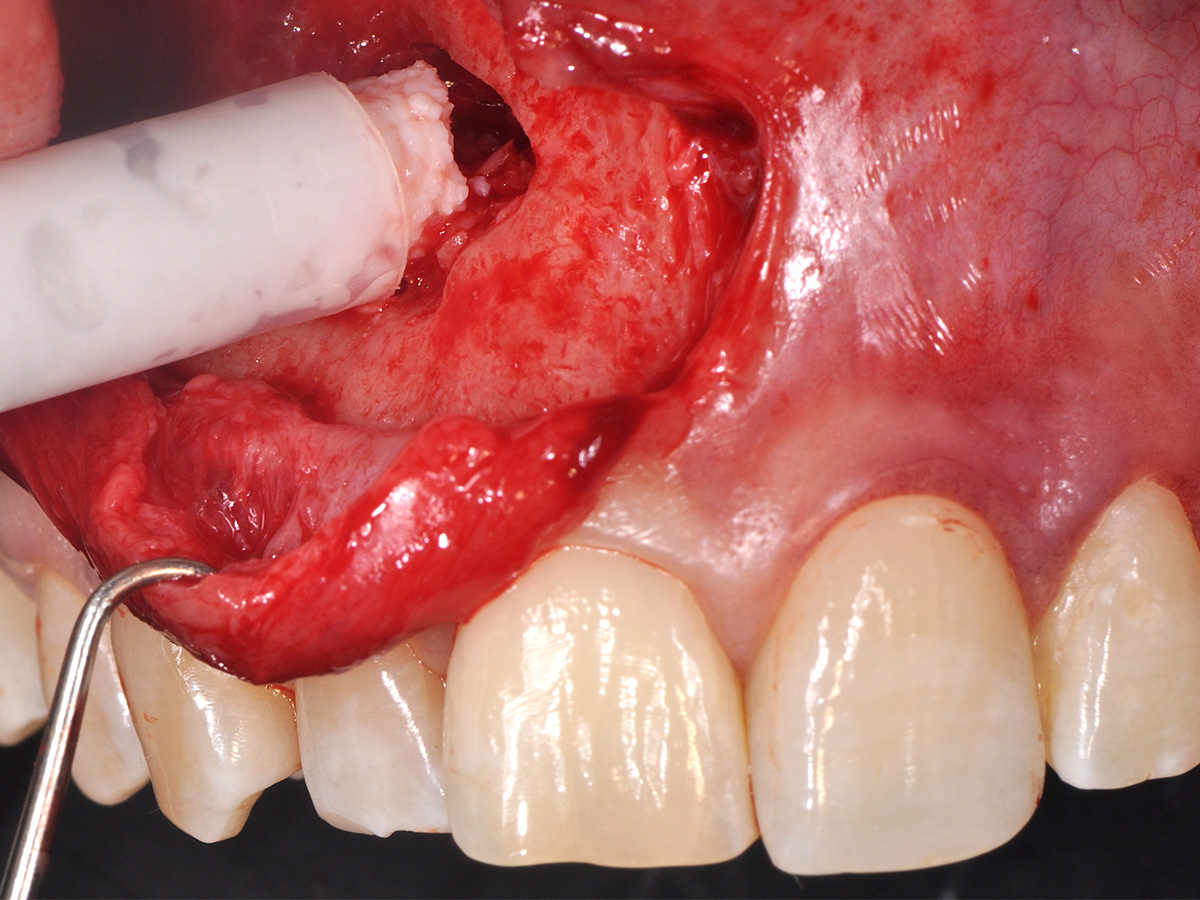

Abbildung 8

Die Schnittführung wurde aufgrund des bestehenden „Gummy Smile“ hoch im Vestibulum geführt...

Abbildung 9

...so konnte die delikate Parodontalstruktur in ihrer Form unangetastet belassen werden, um einen möglichst optimalen ästhetischen Erfolg zu erreichen.

Mit der Patientin wurde der Versuch des Zahnerhaltes trotz ausgedehnter Zyste besprochen. Gleichzeitig sollte das Zystenlumen zu einer sicheren ossären Durchbauung geführt werden, um eine implantologische Sofortversorgung vorzubereiten, falls zu einem späteren Zeitpunkt eine Zahnentfernung notwendig werden sollte. In der Phase vor der geplanten Operation wurden die Wurzelkanalfüllungen an Zahn 11 und 12 durch einen Endodontologen alio loco revidiert. Die Schnittführung wurde aufgrund des bestehenden „Gummy Smile“ hoch im Vestibulum geführt – so konnte die delikate Parodontalstruktur in ihrer Form unangetastet belassen werden, um einen möglichst optimalen ästhetischen Erfolg zu erreichen (Abb. 8, 9). Nach vestibulärer Freilegung wurde die Zyste vollständig entfernt und zur histopathologischen Untersuchung eingesandt (Abb. 10). Anschließend erfolgte eine Wurzelspitzenresektion an den Zähnen 11 und 12 durch die vestibuläre ossäre Perforation (Abb. 11), gefolgt von einer ultraschallbasierten, retrograden Kanalaufbereitung und Abdichtung mit MTA. Um die knöcherne Durchbauung am Boden der Zyste osteoinduktiv zu unterstützen, wurden mit Hilfe eines mechanischen Knochenschabers aus dem Bereich des rechten naso-palatinalen Pfeilers Knochenchips entnommen und als erste basale Augmentationsschicht in den ossären Defekt eingebracht (Abb. 12). Der größere Anteil von 80 % des Defektvolumens wurde mit einem vollständig resorbierbaren, xenogenen Augmentationsmaterial aufgefüllt (Abb. 13) (mp3®, OsteoBiol®). Der Defekt wurde zum Vestibulum hin mit einer stabilen, vollständig degradierbaren Membran abgedeckt (Abb. 14) (Soft Cortical Lamina, OsteoBiol®). Zum einen wurde hiermit im Sinne der GBR das Weichgewebe vom Augmentat getrennt. Zum anderen verhinderte die stabile Membran das Einwachsen eines Weichgewebeankers in den Defekt und damit eine narbige Verziehung im Vestibulum. Um eine Verschiebung der Membran zu vermeiden, wurde diese mit zwei Titanpins in der Kortikalis fixiert. Die Pins wurden bei Beschwerdefreiheit in situ belassen (Titan-Bone-Pin-System). Der Wundverschluss erfolgte einschichtig mit nicht resorbierbarem Nahtmaterial (Abb. 15) (Seralene® 5-0 DS-15). Peri- und postoperativ wurde eine antibiotische Abschirmung unter Fortführung für insgesamt drei Tage mit Amoxiclav 875/125 1-0-1 durchgeführt.